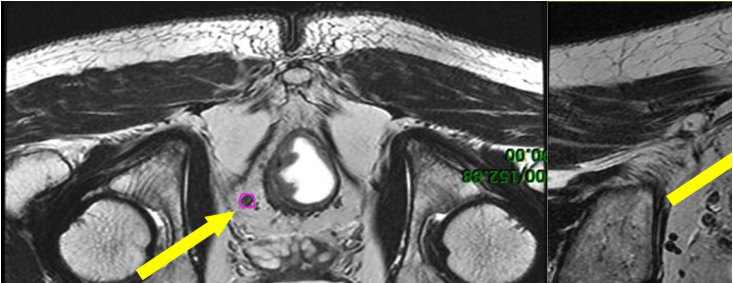

b) GTVnd(粉色) :轉移淋巴結在診斷磁共振或定位磁共振圖像顯示清楚,可參考并輔助在 CT 定位圖像完成 GTVnd 的勾畫(圖 2-圖 4)。

圖 2 直腸癌俯臥位直腸系膜區淋巴結勾畫示例

圖 3 直腸癌俯臥位骶前區淋巴結勾畫示例

圖 4 直腸癌俯臥位淋巴引流區淋巴結勾畫示例